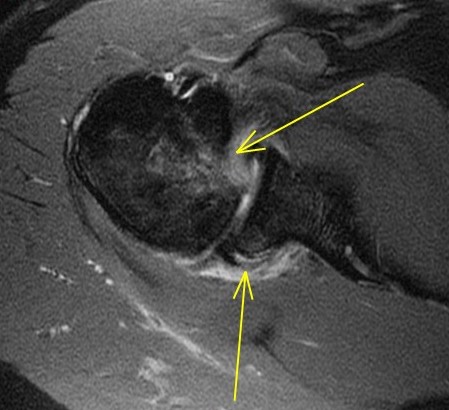

Discussion

Anterior humeral impaction fracture of the lesser tuberosity and posterior labrum tear. The periosteum of the scapula looks intact so maybe should be called a reverse Perthes lesion. Injury occurs when a posterior force occurs to the shoulder (front to back) when the shoulder is internally rotated and flexed. Classic examples are tonic clonic seizure with the patient falling with decorticate rigidity forward and hitting the ground. Also American football lineman in 3 point stance (internal rotation and some flexion) hit by another player moving towards him when the ball is hiked. Typically the other player is as large as a refrigerator.

Diagnosis

Reverse bankart and hill sachs lesions